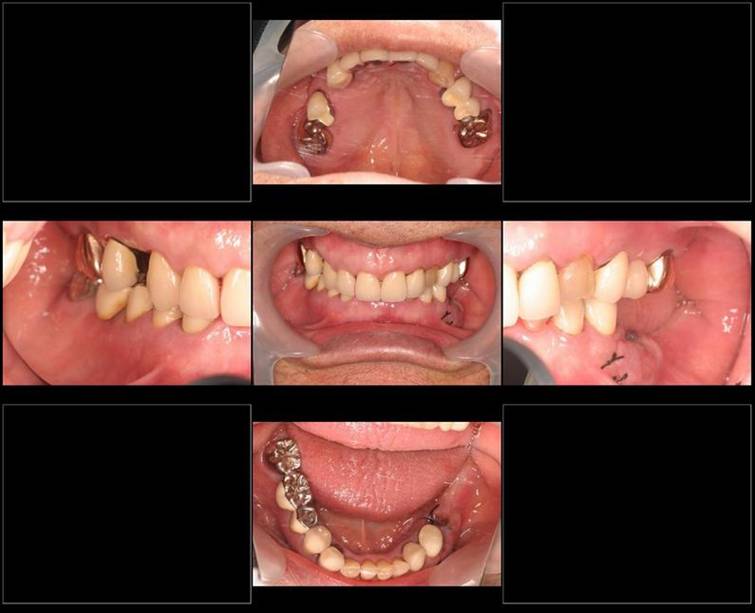

術前。すべての歯が歯周病の末期状態でブリッジ全体がうごいて噛めないとの訴え。右上の犬歯が腫れていました

固定式のブリッジが入っていましたが歯周病で動いています

下顎前歯部には歯石の沈着がみられます